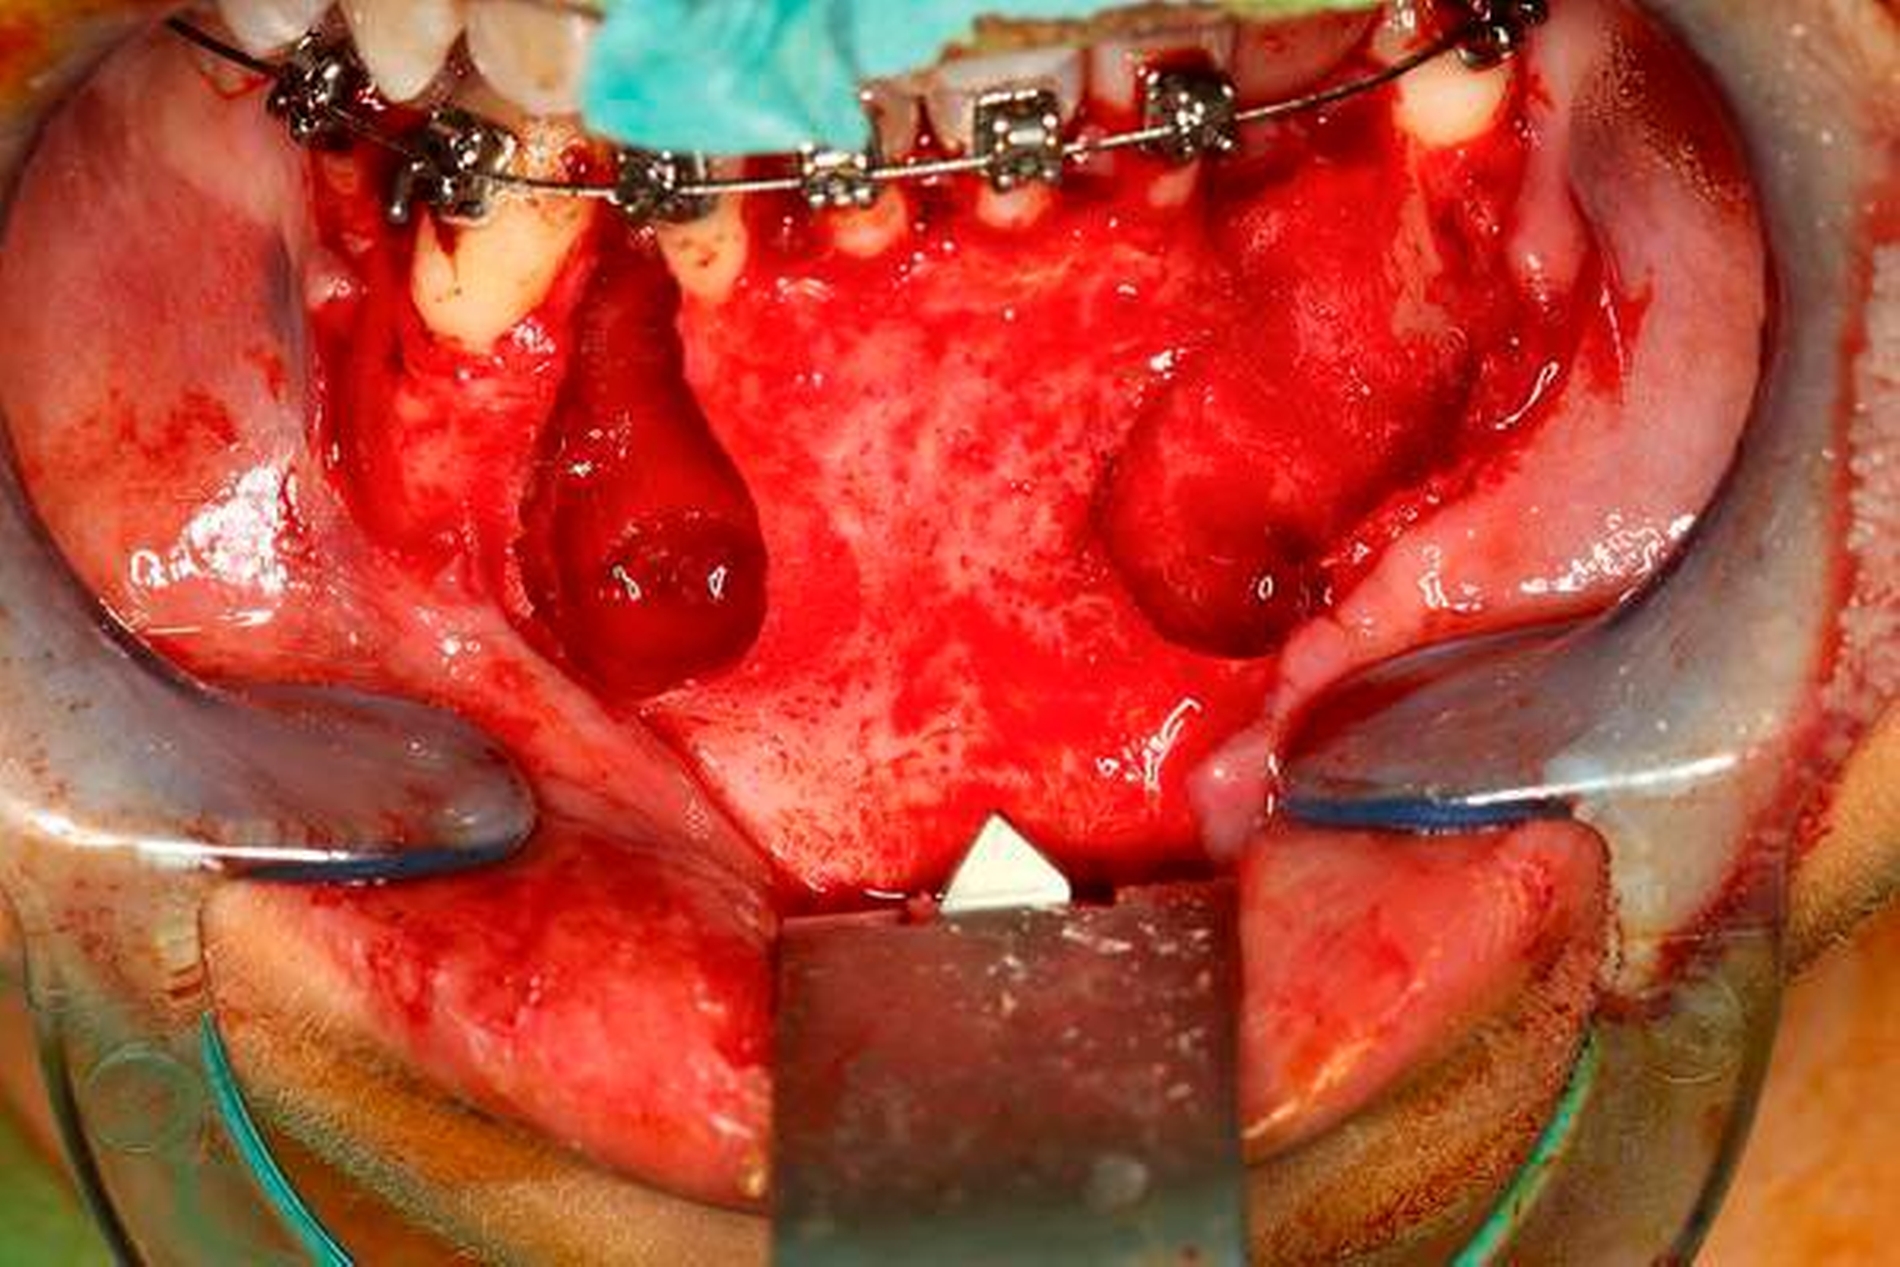

Zur Diagnosesicherung erfolgte eine Probeentnahme aus den zystischen Läsionen. Die pathohistologische Untersuchung ergab die Diagnose zweier odontogener Keratozysten (Abbildungen 7 und 8). Mit dem Ziel des Erhalts der Zähne 34–44 erfolgten die Enukleation der Keratozysten mit peripherer Ostektomie unter Schonung der Zahnwurzeln und die Defektfüllung mit autologer Beckenkammspongiosa und Knochenersatzmaterial (Bio-Oss®, Geistlich) über einen intraoralen Zugangin Allgemeinanästhesie. Im Rahmen desEingriffs wurde der retinierte und verlagerte Zahn 33 operativ entfernt. Abbildung 6 zeigt die postoperative Orthopantomografie mit Beckenkammspongiosa in den Defekten.